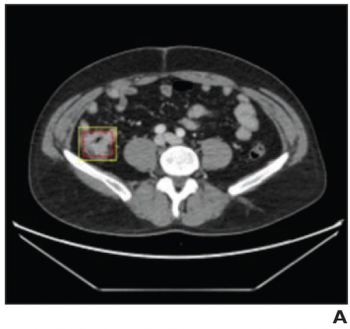

For the assessment of contrast-enhanced abdominopelvic CT exams, an artificial intelligence model demonstrated equivalent or better sensitivity than radiologist readers, and greater than 90 percent specificity for the diagnosis of colorectal cancer.